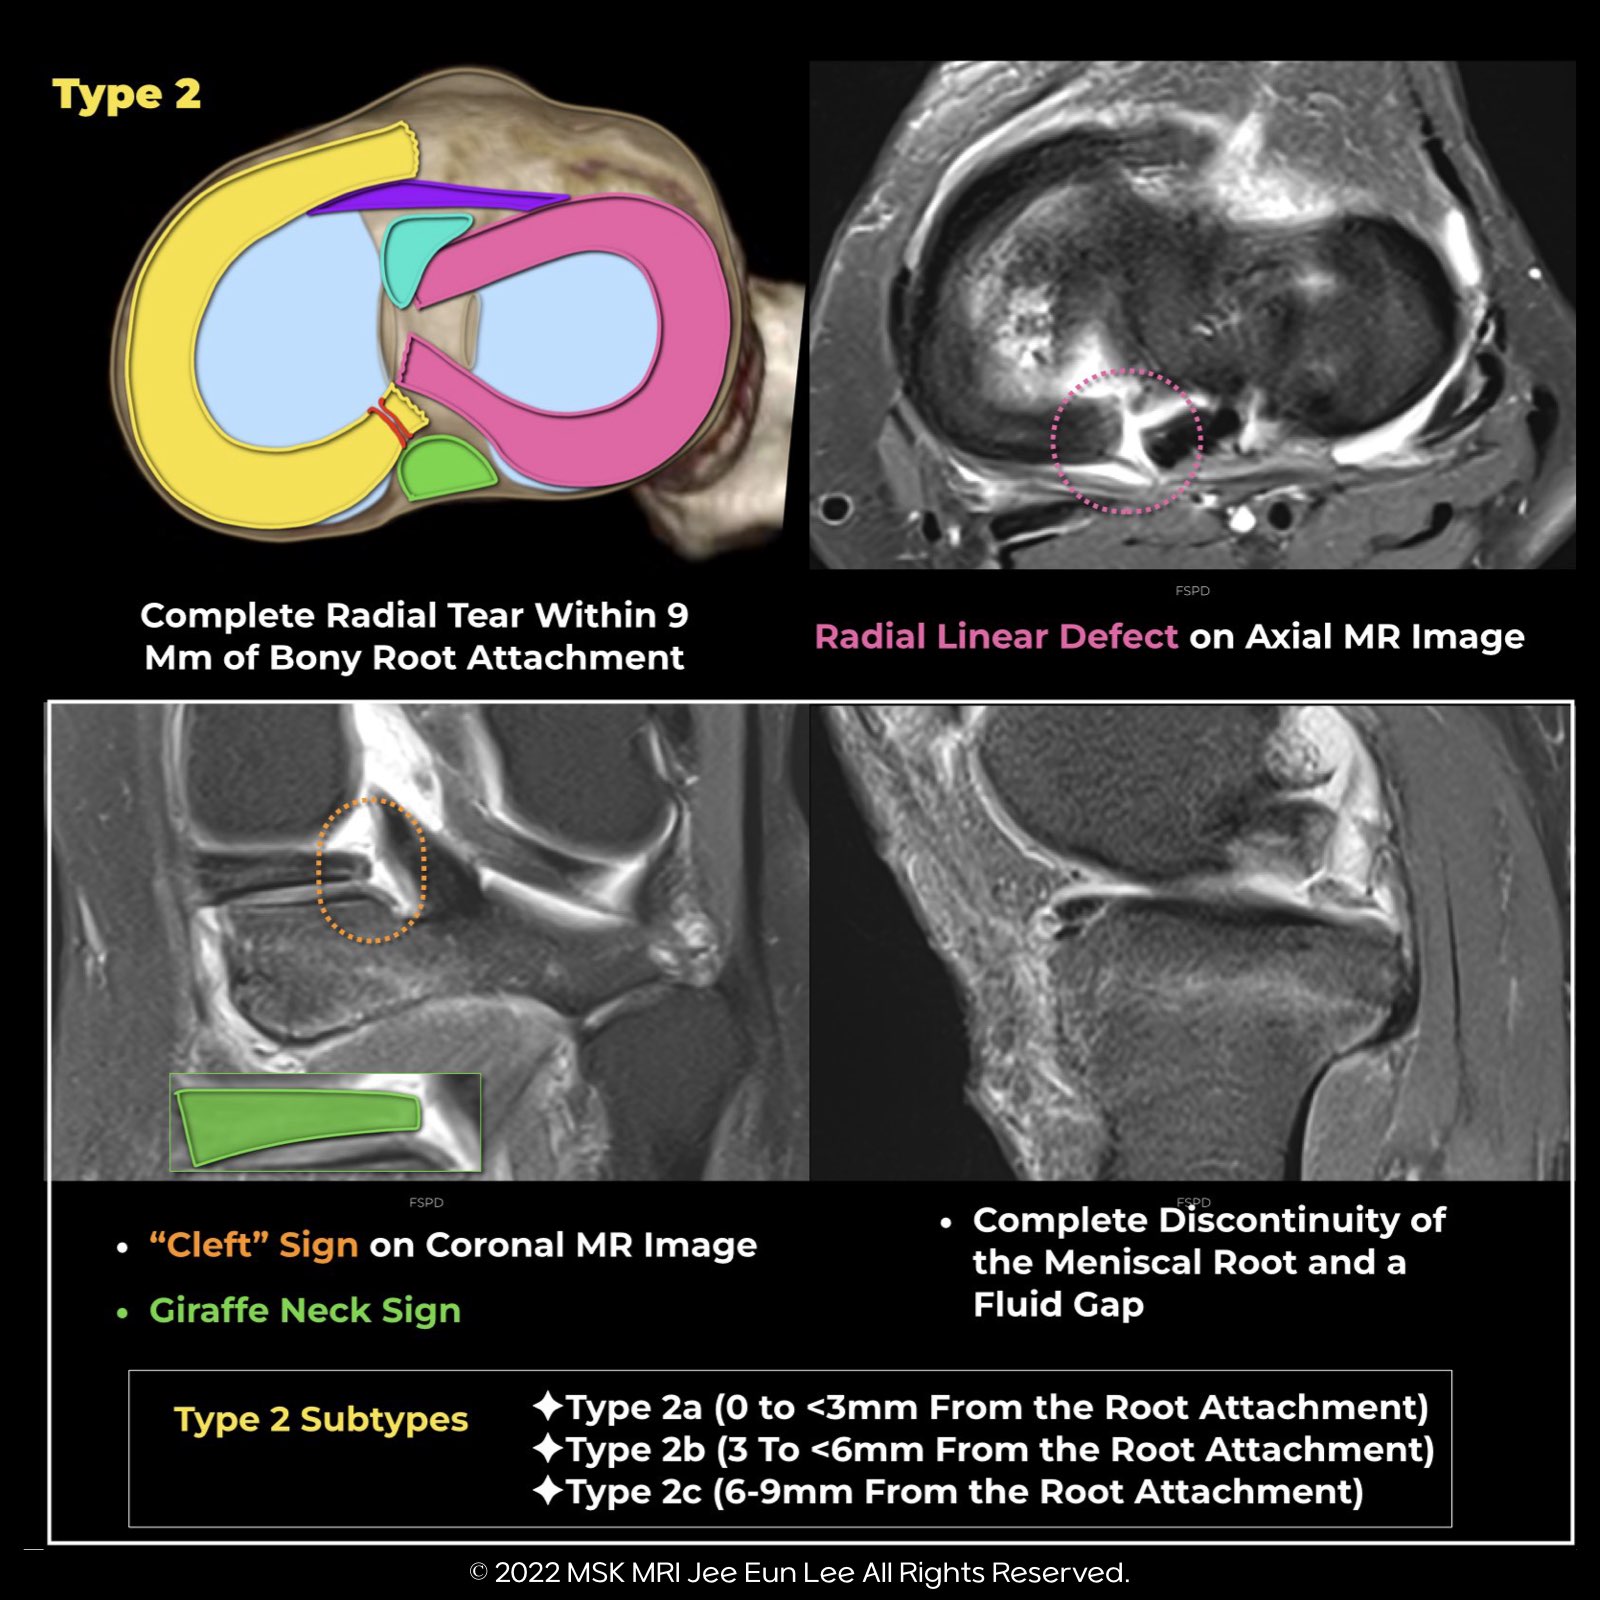

Arthroscopic Classification of Meniscal Root Tears: Type 2

Axial Radial Defect Sign:

- The axial radial defect sign presents as a linear, radially oriented hyperintense signal on an axial image.

Coronal Cleft Sign:

- The coronal cleft sign manifests as a vertically oriented linear or cleft-like hyperintense signal on a coronal image.

Giraffe Neck Sign

- The "Giraffe Neck Sign" refers to a trapezoidal shape of the meniscal body, characterized by a thin inner margin and a larger outer margin. This sign has been recently identified as an indicator of medial meniscus posterior root tears.